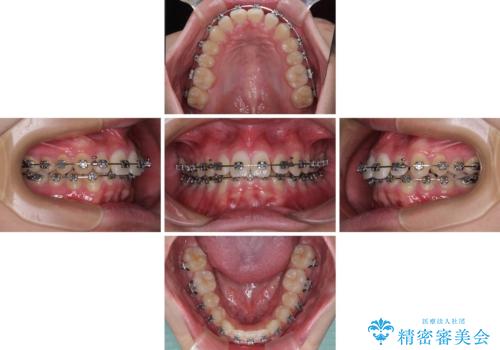

- メタルブラケット

- 1年1ヶ月

- 10-30回

傾斜しいている大臼歯を立ち上げながら、下顎歯列を上顎に対して前方位となるように工夫し、デコボコを解消した上でディープバイトも改善することができました。